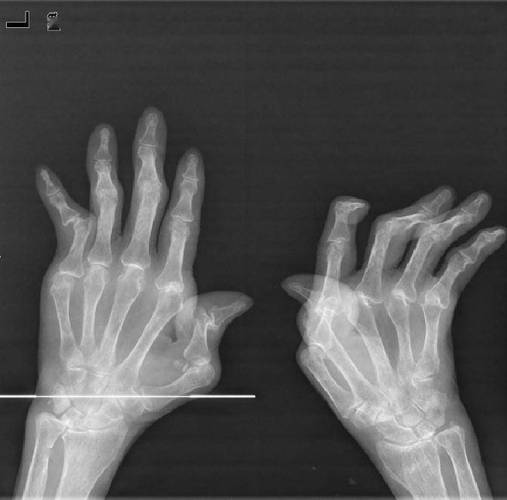

中晚期:出现典型的破坏性改变

如果疾病没有得到有效控制,持续数年后,X光片上就会出现典型的、具有诊断意义的改变:

- 关节间隙狭窄: 这是最关键的X光表现之一,正常软骨在X光下是看不见的,所以关节间隙其实是软骨的厚度,当类风湿关节炎的炎症侵蚀掉软骨后,X光片上就能看到关节之间的空隙变窄了。

- 骨侵蚀: 这是另一个最具诊断价值的特征,炎症的增厚滑膜(血管翳)会像“癌细胞”一样,从关节边缘开始侵蚀骨骼,在X光片上形成边缘清晰的、小洞样的骨质缺损,常见于手指、手腕的掌骨头和指骨的基底部。

- 关节畸形: 当软骨和骨骼被严重破坏,关节周围的韧带和肌腱也因炎症而松弛或断裂时,关节就会失去正常的对位关系,导致畸形,例如手指的“天鹅颈”样畸形、“钮扣花”样畸形,手腕的尺偏畸形等。

- 骨性强直: 在极晚期,严重的骨侵蚀和修复反应可能导致关节面完全融合,活动完全丧失,这在X光片上表现为关节间隙消失,骨头长在了一起,类风湿关节炎更常导致的是纤维性强直(活动受限但X光上没长死),骨性强直相对少见。